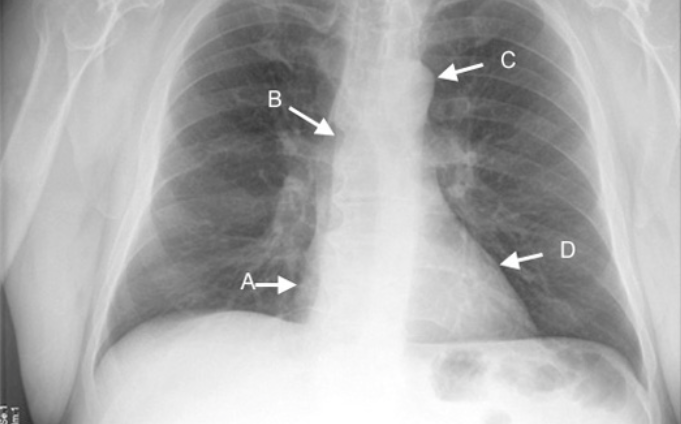

Identify A.

What is the disease when it is not visible?

Right Heart Margin

Right Middle Lobe Disease

Identify B.

Ascending Aorta

RU Lobe Disease

Identify C.

Aortic Knob

LU Lobe Disease

Identify D.

Left Heart Margin

Lingular Disease